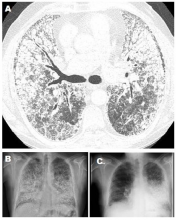

Figure 1. A) CT scan shows PAM findings. B) Chest X-rays previous to SLT. C) Chest X-rays 6° month follow-up right SLT.

The authors report the case of a 58-year-old nonsmoking man, with a medical history of bronchial asthma, who was otherwise healthy and who had a sister diagnosed with PAM. In 2007 he presented with progressive dyspnea. His CXR showing generalized nodular opacities and a CT scan showed multiple nodules of calcium density with an alveolar distribution that affected all lobes, septal and reticular thickening with predominance in the pulmonary bases, and small subpleural cysts (Figures 1A and 1B). After a nine-year period of medical management and follow-up with evidence of progression of respiratory dysfunction, the patient was referred for pretransplant evaluation with Medical Research Council grade III dyspnea. Respiratory function tests indicated a FVC 61%, FEV1 65%, Tiffenau index 105%, TLC 65%, and DLCO 32%. Resting arterial blood gas values on room air included pH 7.45, pCO2 32 mm Hg, pO2 59 mm Hg, HCO3 22 mmol/L, and SatO2 93%. The patient’s six-minute walk test distance was 330 m with O2 at 6 L/min, initial SatO2 was 98% and final SatO2 was 79%. Echocardiogram reported no pulmonary hypertension, a right ventricle ejection fraction of 51%, and a left ventricle ejection fraction of 67%. The CXR diameters were 19 cm right vertical, 21 cm left vertical, and 29 cm horizontal. Perfusion scintigraphy showed 54% of flow to the right lung. The authors decided to perform a single lung transplant (SLT). After 160 days on the waiting list, a right SLT was performed through a clamshell approach, finding a brownish and indurated lung parenchyma with marked bone metaplasia (Figure 2). A right pneumonectomy was performed after a pulmonary artery clamping test. The bronchial anastomosis was performed with continuous anterior and posterior nontelescoped sutures, and the vascular anastomoses were performed with monofilament running suture according to usual technique. During the reperfusion, there were no incidents and the ischemia time was 285 minutes. The patient was extubated after 24 hours and stayed in the intensive care unit for seven days. The postoperative clinical and radiological course was favorable with no incidents or complications, and the patient was discharged after 30 postoperative days in good condition. Clinical and radiological follow-up six months after transplant were satisfactory (Figure 1C).